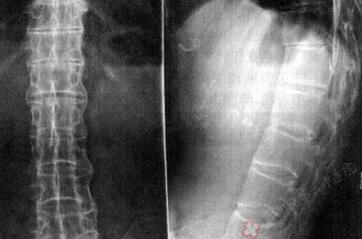

萧先生由于经常面对电脑工作,总感觉颈部僵硬,左上肢抬举困难,早上起床时背部僵硬。时间长了,这些症状发作频率越来越高,不安的萧先生抽空去了医院检查,经检查确诊为强直性脊柱炎。尝试了多种治疗方法,...[详细]